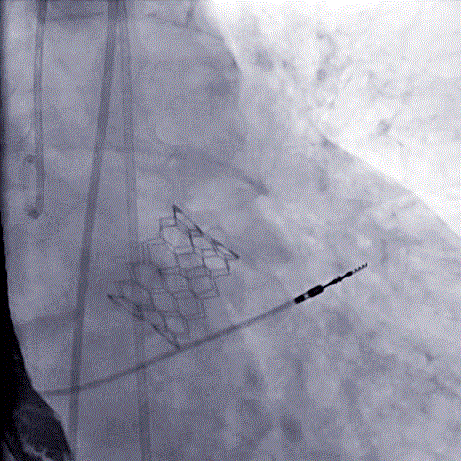

病例3

患者男性,80岁,因“胸闷气促2月”入院。术前心脏超声提示主动脉瓣钙化,重度狭窄伴中度反流,峰值流速4.7m/s,跨瓣压差53mmHg。CT评估结果显示主动脉瓣重度钙化,瓣环平均直径25.8mm,瓣环面积507.3mm²。左冠脉开口高度12.1mm,右冠脉开口高度18.0mm。

3名患者均经详尽影像学重建、评估及病例讨论,测量瓣环直径,评估冠脉梗阻风险,评估外周血管条件后,经股动脉入路分别植入 25#、21#、25#Renatus介入主动脉瓣。手术平均耗时1小时左右,3名患者全程生命体征平稳,出血极少。最终介入主动脉瓣植入位置理想,功能表现出色,左室造影及经食道超声观察无瓣周漏及反流。各患者术后主动脉瓣峰值流速及跨瓣压差均降至正常。

球扩瓣释放(病例3) 术后造影(病例3)